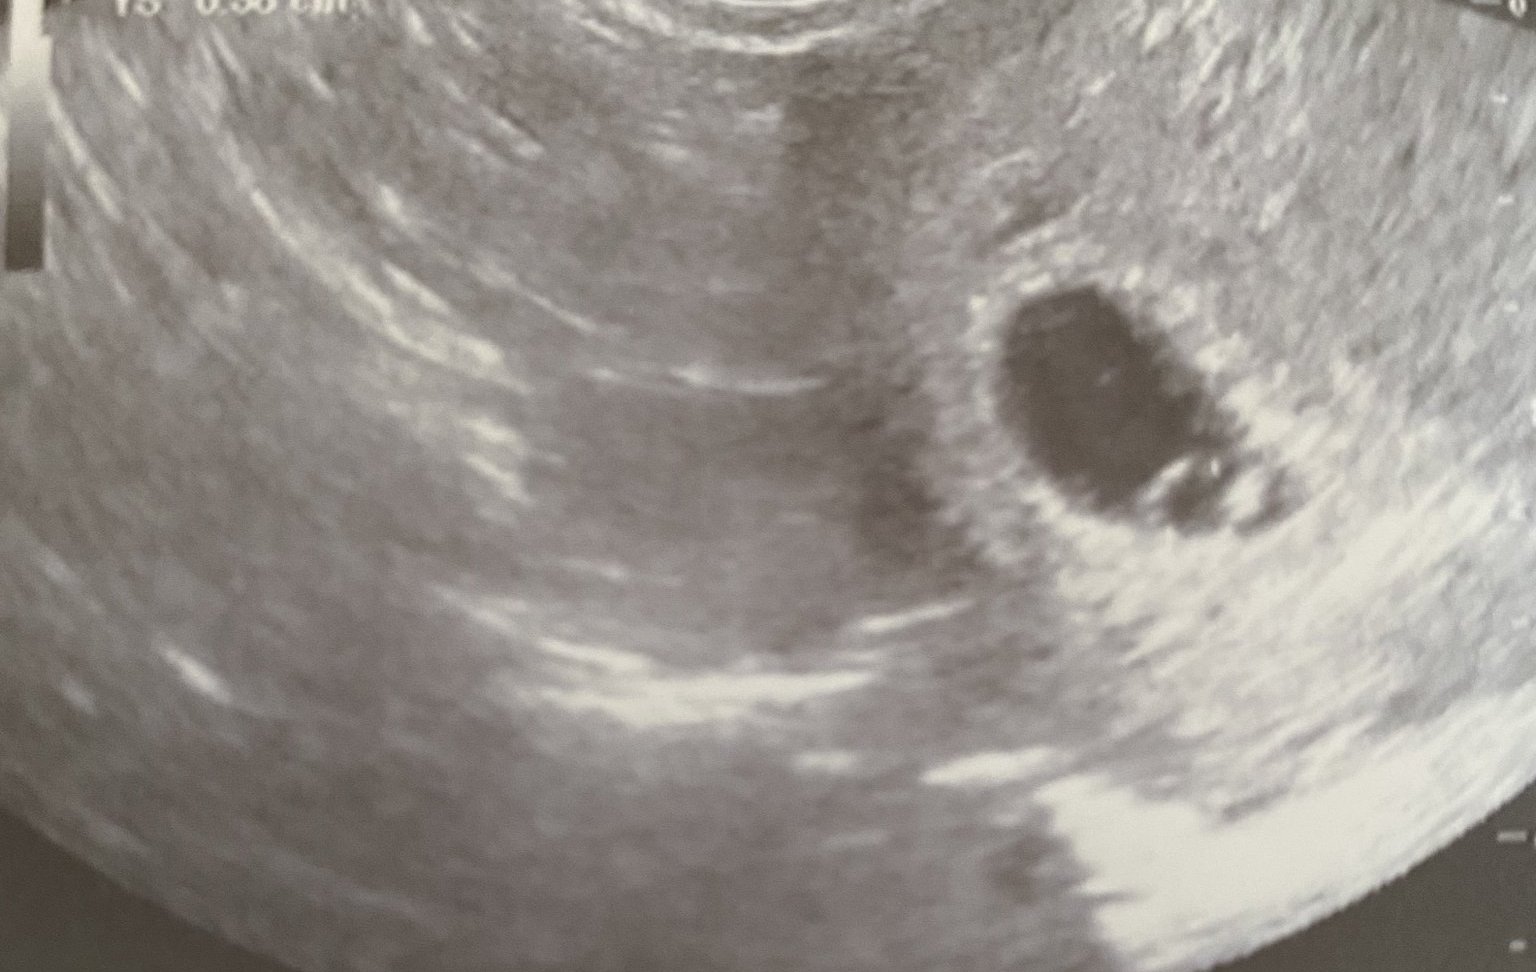

Днес бях при него за първи път и първи преглед в 5+1г.с

Установихме вътрематочна бременност на около 5 седмици(по думите на док).Започвам ацетизал кардио заради тромбофилия и ми изписа еутирокс , тъй като на последното изследване тсх беше леко завишено.Аз утре ще си пусна обаче пак да видя какво е що е.

Иначе аз преди малко се прибрах от преглед при новия док 😄, много го харесах , обяснява, отговори на всичките ми припряни въпроси изчерпателно, има хубава апаратура и видяхме жълтъчен мехур с ембрионче и сърдечна дейност - 5с. 3д. И мисля да съм си при него вече

Да на вагинален ехограф гледат до 3-тия месец, иначе нищо не се вижда, но си в легнало положение.

Аз изобщо нямаше да ида толкова рано ако нямах предистория с извънматочна, и от страх да не ми е запушена и другата тръба трябваше да ида възможно най-рано, ако има нещо да го видим в началото. Сега щом е в матката значи ми е отпушена тръбата, което ме успокоява, дори и сега да не се получи ще е другия път! Всичко може да се случи, важна е положителната нагласа, и аз постоянно се оплаквам, ама не ви ли олеква така като се оплачете на група непознати жени..😄😂